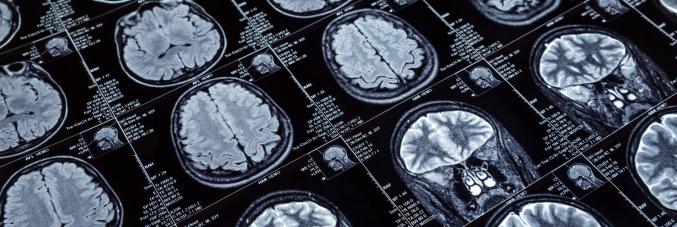

Che area del cervello usano matematici e artisti? Lo dice una mappa